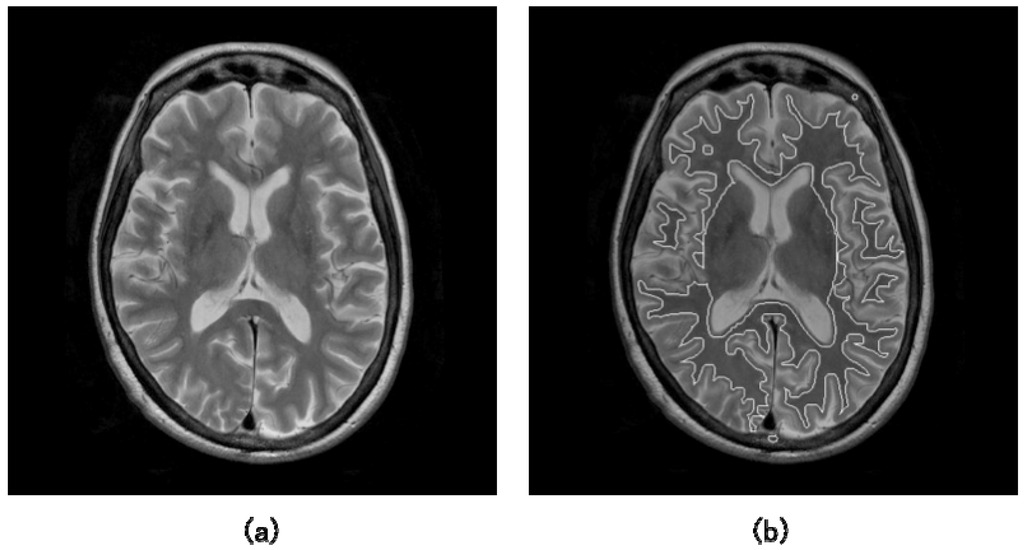

where t is the time and F is the speed function. While updating the level set function, the zero level set ϕ = 0 moves according to the speed function in the higher dimensional level set function. Here, the zero level set is called as “moving front”. Finally, the update of the level set function was stopped if some conditions are satisfied. Figures 7(a) and 7(b) show the illustrations of an original T2-weighted image and white matter regions segmented by a level set method, respectively [55].

Figure 7.

Illustrations of: (a) an original T2-weighted image and (b) white matter regions segmented by a level set method [55].